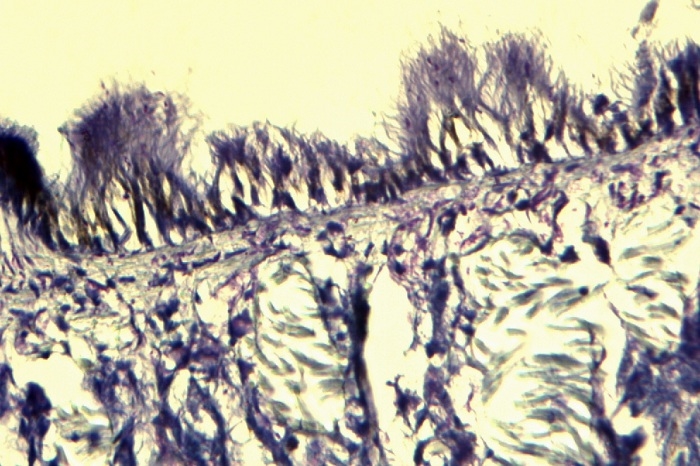

Du hast mich gefragt um den gleichen Schilddrussenschnitt nochmal zu Fotografieren mit mein Orthoplan und Moticam 2300 um ein vergleich zum Novex zu bekommen.

Natürlich ist den vergleich nicht Gans Fair weil es in diesen Tread handelt um ein Mikroskopvergleich und hier spielt die Kamera eine wichtige rolle aber was die Moticam mit das Orthoplan Schaft, Schaft er nicht mit ein Novex. Das ist klar!

Hier die Aufnahme von ein Coolpix 4500 an mein altes Novex B

Ich habe alles durchmustert aber den exakt gleiche stelle kann ich nicht finden weil den Schnitt im Mülleimer belandet ist.

Das gleiche Block habe ich jedoch noch und hier sind aufnahmen davon.

Färbung ist auch eine HE und den Objektiv habe ich hier 16x gewählt und so kommt es ungefähr überein mit das Bild am Novex.

Schau mal hier, zwei Pfeilpunkte, wie scharf das feine Endothel von ein Lymphgefäß dargestellt wird.